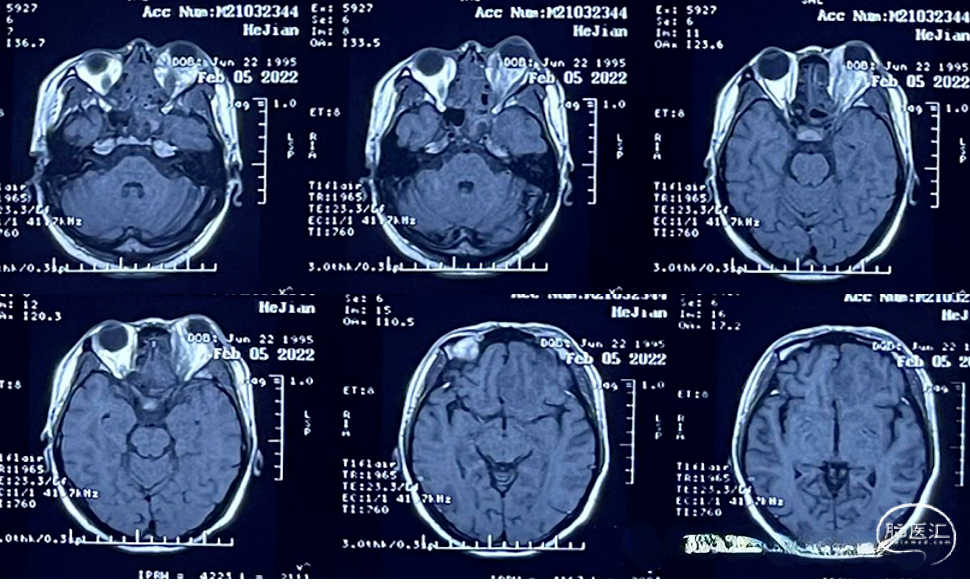

2022.02.05MR:鼻腔,眼眶内感染范围继续扩大,额叶脑组织水肿明显,但并无脓肿形成。

2022.02.07 MR:鼻腔,眼眶内呈现术后改变,额叶水肿范围逐渐局限。